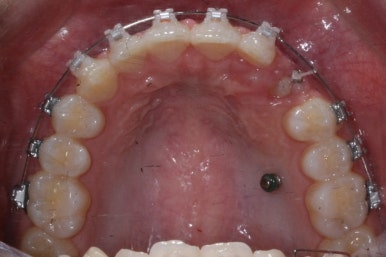

위 사진들은 부산매복치아교정 키다리아저씨치과에 처음 내원하셨을 때의 모습입니다.

화살표 표시한 부분이 바로 영구치 송곳니가 있어야 할 자리인데, 매복이 되어있고 대신 유치가 여전히 남아있는 모습입니다.

환자분의 나이가 만으로 15세였는데, 치과에 처음 올 때 해당 치아가 영구치가 그냥 썩은 줄 알고 오시는 경우가 많습니다.

X-ray를 찍어보고 하면 그 때서야 해당 치아는 유치이며 영구치 송곳니는 뼈 속에 묻혀 있는 것을 알게 되지요.

보통 송곳니는 초등학교 5학년 전후로 나오게 되는데, 이 환자분은 유치가 남아있는 것을 마치 영구치가 나온 것으로 착각하셨던 경우입니다.